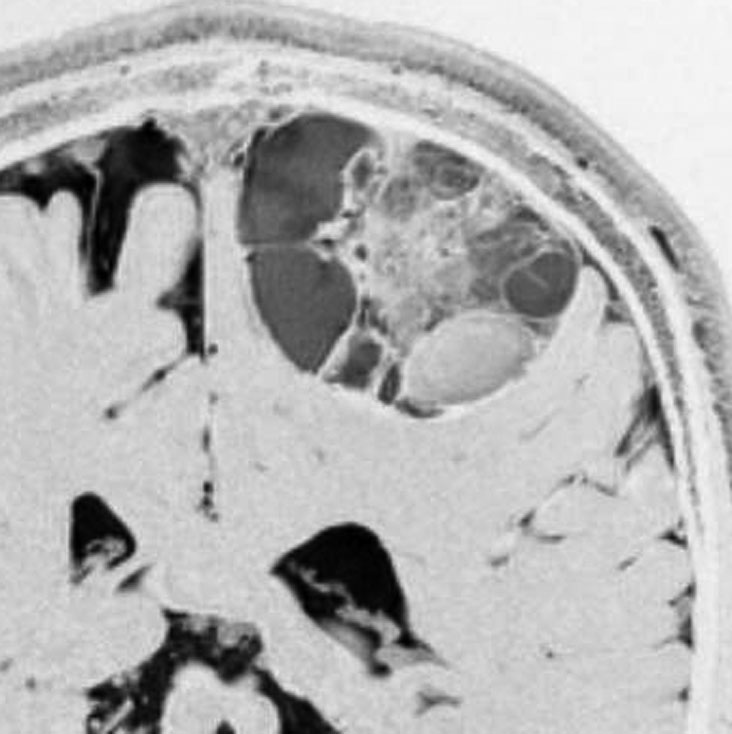

成人の大脳皮質のう胞性毛様粘液性星細胞腫

症候性てんかんで発症した30代の毛様粘液性星細胞腫です。術前診断で,のう胞性髄膜腫 cystic meningioma と間違えました。腫瘍内でごくわずかに出血していました。毛様細胞性星細胞腫は腫瘍内出血をしばしば生じます。実質部分はガドリニウム増強されていて多房性のう胞があります。成人型の毛様粘液性星細胞腫としては全く矛盾のない画像なのですが,発生した部位が頭頂葉皮質だったので術前診断できませんでした。eroquent areaなので完全摘出する必要はありません,のう胞壁を取り残しても再燃しません。